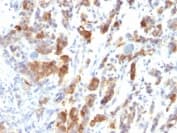

Anti-Mucin 5AC antibody [MUC5AC/917](ab218466)

Mouse Monoclonal Mucin 5AC antibody. Suitable for IHC-P and reacts with Human samples. Cited in 3 publications. Immunogen corresponding to Recombinant Fragment Protein within Human MUC5AC.